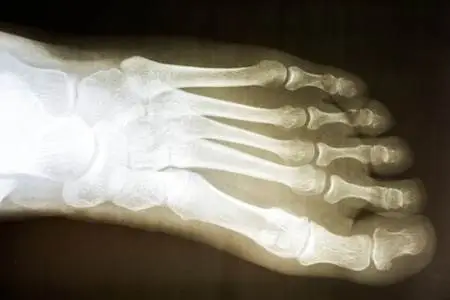

X-rays & Cuboid Syndrome

X-rays, CT scans, and MRIs are often not particularly helpful in diagnosing cuboid syndrome unless used to rule out other, more serious foot conditions.